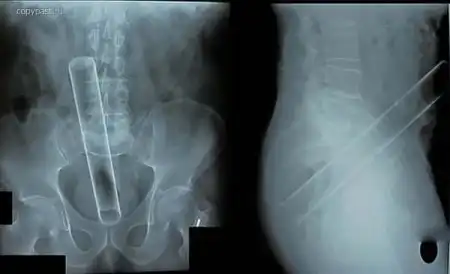

Пациент со стеклянной цилиндрической мензуркой в анусе. На уроках химии такого

не проходили